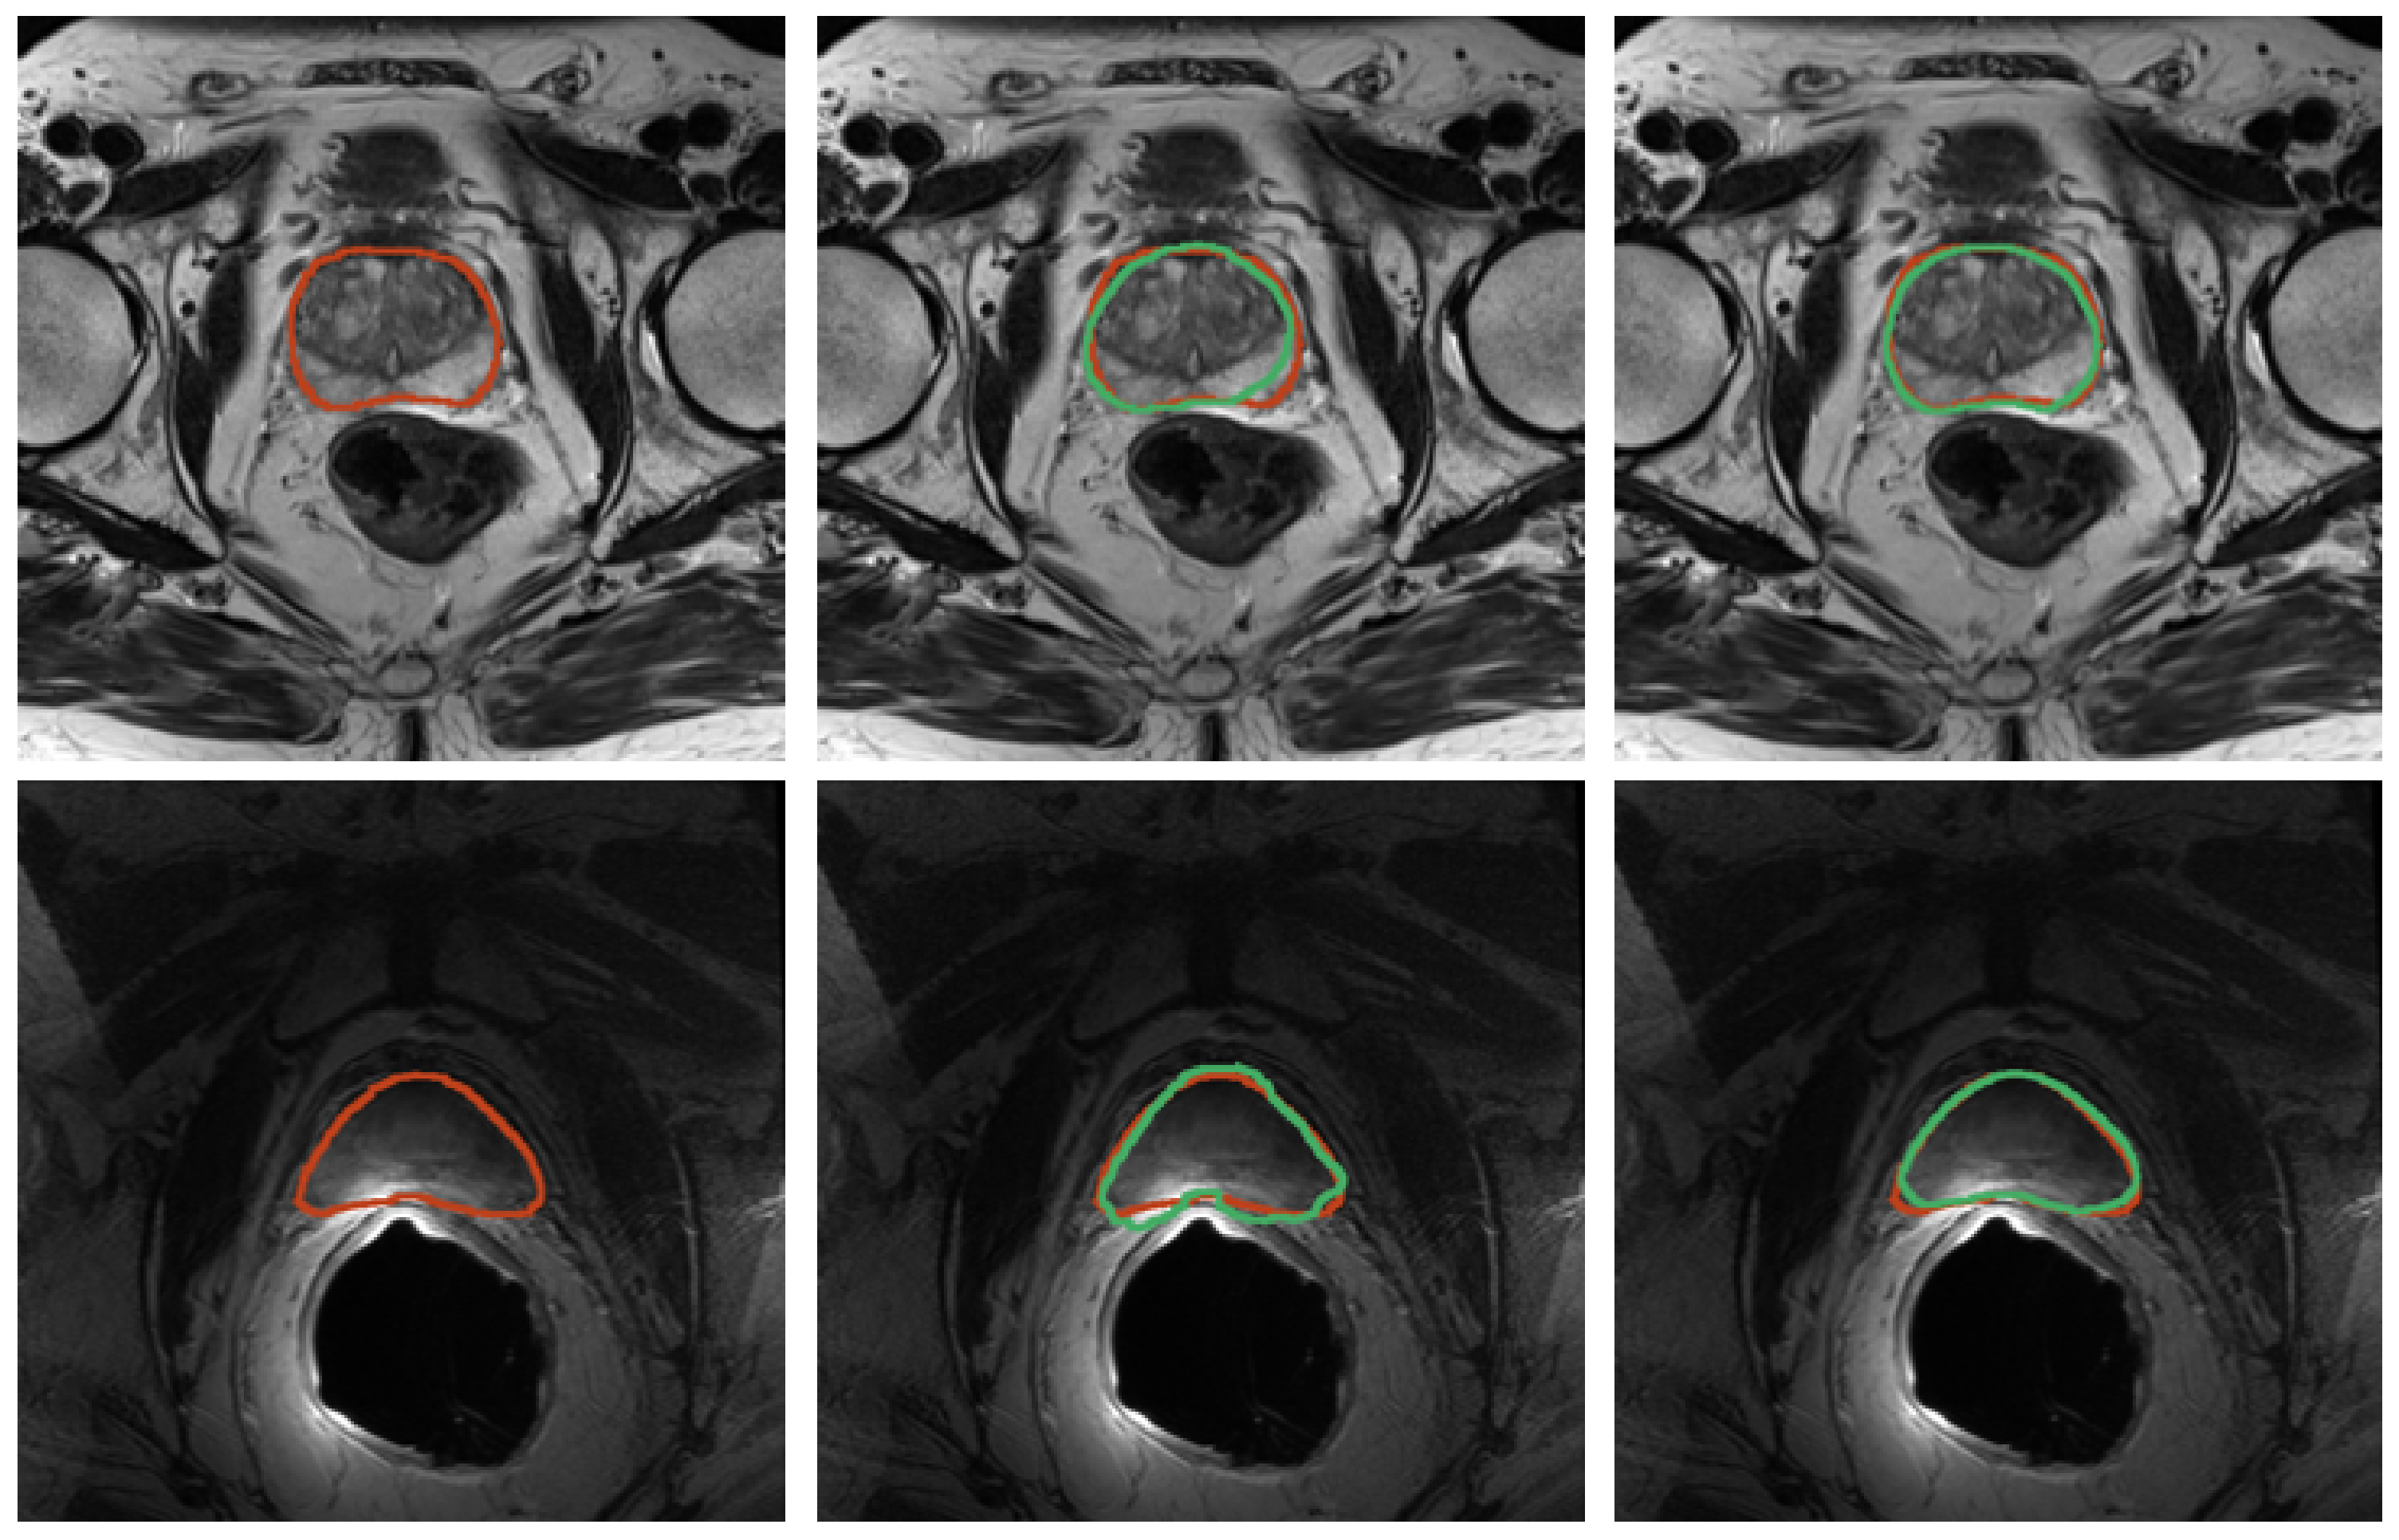

Figure 9.

Results for prostate segmentation from TRUS. The left image portrays the ground-truth prostate mask in red. The right image depicts the segmentation results after both the first and second iteration in green and yellow colors, respectively.